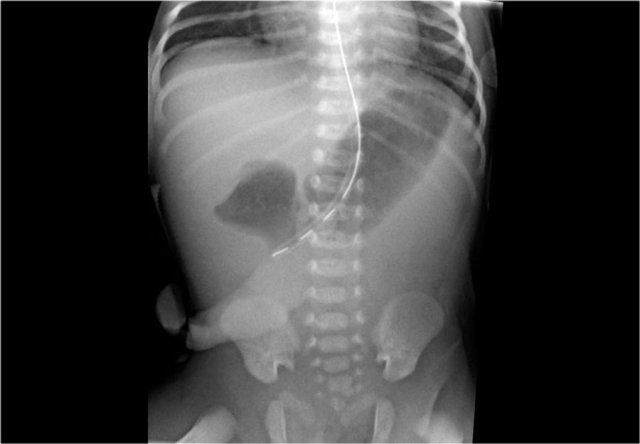

The images show a typical case of NEC with pneumatosis intestinalis.

On the horizontal beam image there is no sign of free air.

Here images of a neonate who developed NEC.

At this early stage the radiograph only shows non-specific bowel dilatation.

At this stage you cannot make the diagnosis.